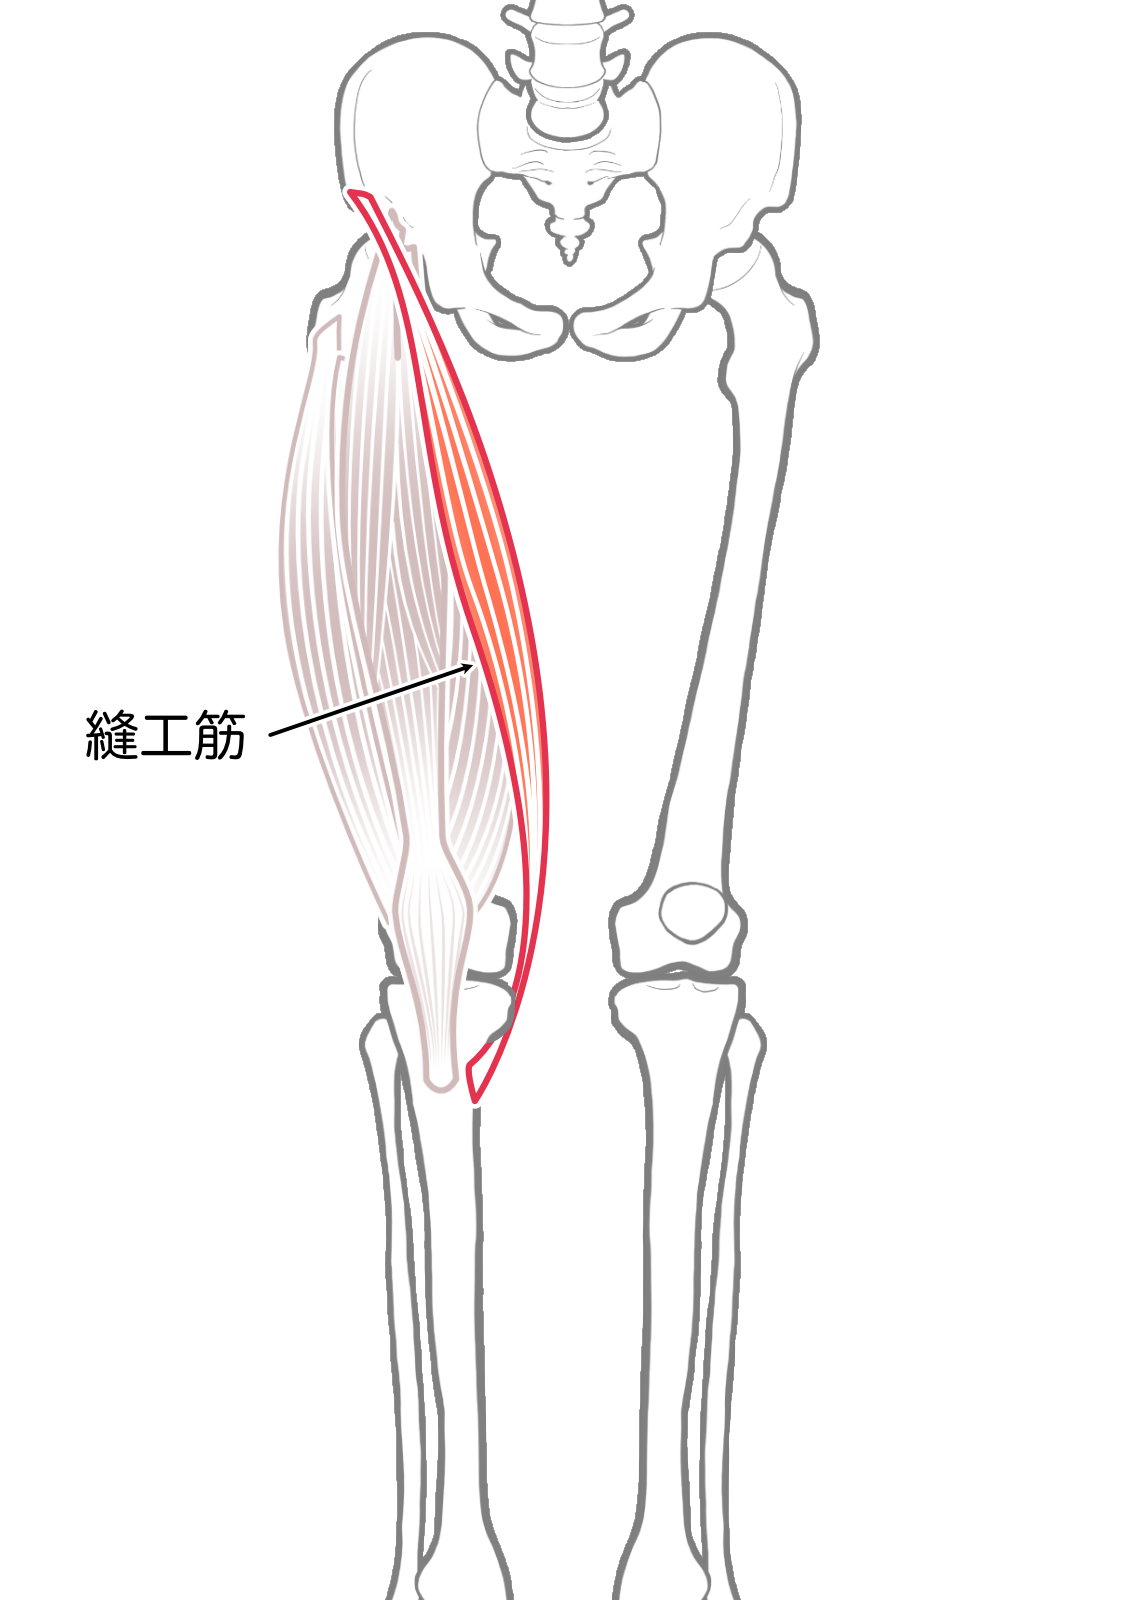

縫工筋

| 起始 | 上前腸骨棘 |

| 停止 | 脛骨上部内側面(鵞足) |

| 神経 | 筋大腿神経L2-3 |

| 作用 | 膝関節屈曲,内旋 |

- 縫工筋

- 縫工筋